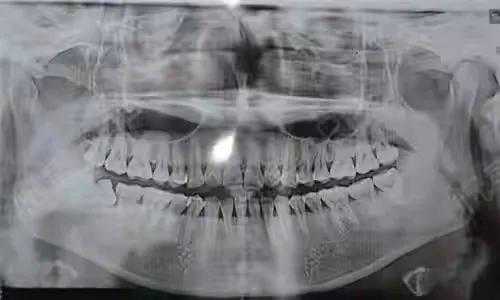

step1.

先要做一个口腔全景片、颌骨CT等。查看口腔的具体情况,是否有炎症、牙槽骨吸收等情况。然后,医生会询问患者全身的病史,可能需要查血常规、出凝血时间、血压、血糖、乙肝5项、脉搏等。确定能手术后,才会诊断去模、指定种植牙方案。(第一次大约1个多小时)